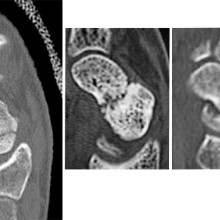

X-rays of scaphoid fracture

From left to right: Normal scaphoid fracture. Scaphoid fracture that is struggling to heal. Scaphoid non-union where the bone has failed to heal.